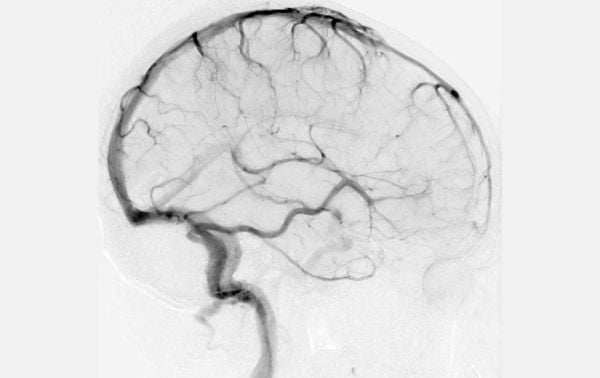

Cerebral Angiography (1927)

Developed by Egas Moniz, this method used contrast dyes injected into the bloodstream to make brain blood vessels visible on X-rays.

Though invasive, it was revolutionary for diagnosing brain tumors and vascular conditions. This technique is still used today in a safer, refined form.